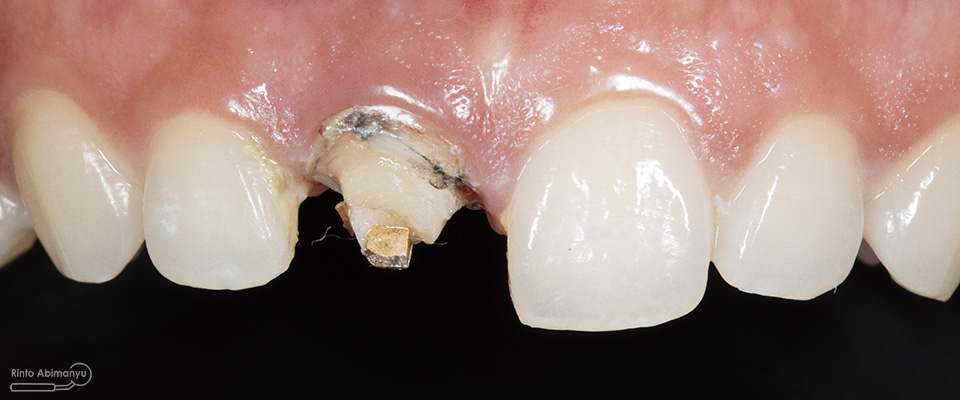

Begini kondisi klinis saat datang…

Foto klinis gigi-gigi anterior yang mengalami fraktur

Dari pemeriksaan radiografis lokasi fraktur menyerempet kamar pulpa pada ketiga gigi tersebut… Saya sampaikan kepada pasien bahwa ketiga gigi tersebut memerlukan perawatan saluran akar terlebih dahulu baru kemudian dilanjutkan dengan restorasi indirek… kenapa saya pilih restorasi indirek? Pertimbangannya adalah sisa struktur mahkota gigi yang ada bila hanya di “sambung” dengan restorasi direk dalam jangka panjang rentan mengalami kerusakan, yang kedua pemilihan warna akan lebih maksimal pada kasus ini…. Pasien setuju dengan rencan perawatan yang saya jelaskan…